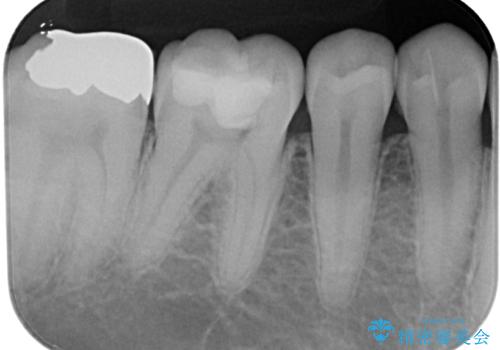

頬の筋肉の痛みではないことと上顎の歯に問題がないことは確認ができましたが、下顎の最後臼歯か手前の歯であるかの診断は、非常に難しいものとなりました。

レントゲンやCTでは手前の歯の方が疑わしいように思えましたが、冷熱や電気刺激の反応から正常と判断されました。

最後の確認方法として、局所麻酔を行わずに最後臼歯の銀歯を外し、神経組織近くまで歯質を切削したところ痛みなどを全く感じず、その後無菌的環境下にて切削を進めたところ、神経組織の一部が壊死していることが確認されました。